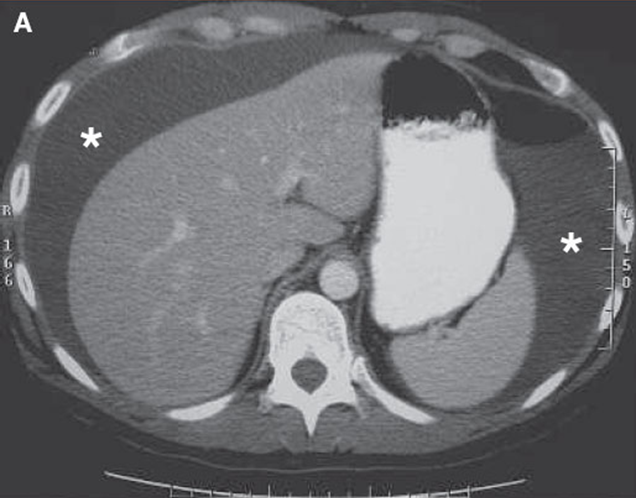

Splenomegaly

Ascites

Fluid in the peritoneal cavity

This is not a primary pathology. This is always a symptom of a bigger pathology

Common causes are:

Cirrhosis

Carcinoma